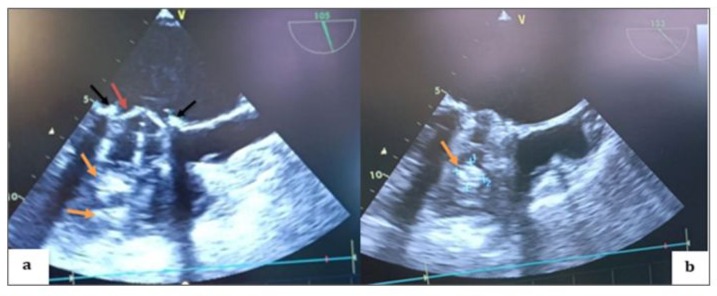

General anesthesia induced: 250 µg fentanyl, 0.3 mg/kg etomidate, and 1.2 mg/kg rocuronium. Anesthesia maintained with sevoflurane (MAC = 1.0). Analgesia maintained: 250 µg fentanyl boluses every 30–40 min; blood gas analysis 10 min after intubation. TEE probe inserted using video laryngoscope. Patient stable with low-dose vasoactive support before cardiopulmonary bypass. Doppler ultrasound in Scarpa triangle to study femoral vein and artery, found to be patent but small in size, especially femoral artery (8 mm). TEE performed pre-sternotomy to define anesthesia and surgical strategy, evaluate lesions, and address hemodynamic instability before CPB. Bicaval view used to monitor venous cannula progression. (video 1) Upon opening Scarpa triangle, common femoral artery was smaller than available venous cannulae. Central cannulation was decided upon, with TEE monitoring throughout. LV appeared small with limited opening of one valve leaflet and complete blockage of the other. Mitral valve apparatus identified with thrombi. Anterior and inferior walls of LV retained kinetics. Oblique plane revealed LV inflow chamber and outflow tract. Right ventricle was dilated with normal aortic ring. Leaking annuloplasty seen in right atrium. Left atrium, tricuspid valve, and right ventricle were thrombus-free. In mid-esophageal view, St. Jude mechanical valve had thickened ring with thrombi on both sides. (Figure 3) Pulsed Doppler TEE at the mechanical mitral valve in the mid-esophageal view, at a perpendicular plane of 60 degrees, showing a holosystolic retrograde mitral flow velocity of 1.3 m/s. (video 2) Slight probe rotation revealed left atrium dilation, thickened leaflets, limited leaflet movement at heart crux, and blockage at atrium-ventricle junction. Hyper-echoic thrombi in left ventricle were partly obscured. (Figure 3b) TEE in 2D mode, transducer at 45° counter clockwise rotation, shows dilated left atrium with obstructed mechanical valve due to multiple thrombi at leaflets, ring, and core. Leaflet opening beneath appendage is absent and limited on opposite side. Ring appears thickened with fibrinous thrombus. Reverberation echoes obscure left ventricle walls except for anterior and inferior walls with preserved kinetic activity (Video 3).

2D TEE in a mid-esophageal view at 105-to-135-degree angle, showing thrombi on atrial and ventricular side of mechanical valve, a thicken appearance of valve ring and multiple thrombi (Video 4).

TEE in colour Doppler mode centered on the thrombosed mechanical mitral valve, showing significant mitral regurgitation reaching the depth of the left atrium. (Video 5) At 105 to 145 degrees, 2D TEE in a mid-esophageal view, The septum and mitral valve had thrombi on both sides and a thickened valve ring. Multiple thrombi were on the ventricular side. Mean transvalvular gradient was 27.85 mm Hg with VTI of 109.4 cm, indicating stenosis. Severe mitral regurgitation was observed with a gradient of 28.80 mm Hg.

Figure 3: TEE in mid-esophageal view, transducer at 0 degrees, showing a thickened appearance of the St. Jude mechanical valve ring in an anatomical anti-position (a) (red arrow) with multiple thrombi on the atrial (a; b) (black arrow) and ventricular (b) (orange arrow) sides of both the internal and external leaflets.

Figure 4: TEE 2D in the mid-esophageal view, transducer at 105 degrees (a; b), showing thrombi on the atrial side of both the internal and external leaflets of the mechanical valve on the aortic valve side as well as on the opposite side (black arrows), with a thickened appearance of the mechanical valve ring (red arrow) and multiple thrombi on the ventricular side (orange arrows).

Figure 5: TEE Doppler with the transducer at 105 degrees showing a very high mean transvalvular gradient of 27.85 mm Hg on continuous Doppler, with a calculated valve area of 109.4 cm² (a) in favor of stenosis, and severe thrombotic regurgitation with a mean gradient of 28.80 mm Hg (b) in favor of severe mitral regurgitation.